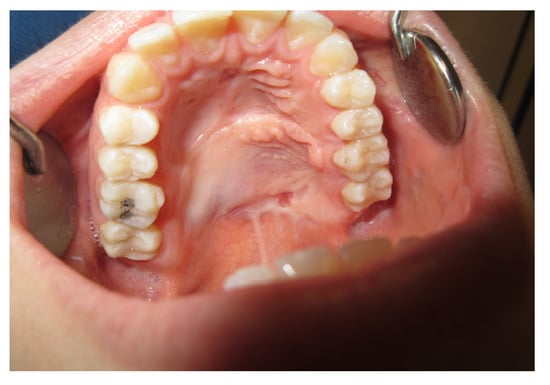

3.1.2. Case 2: P.S.

| P.S. | X | * | 7 | 0 | ||